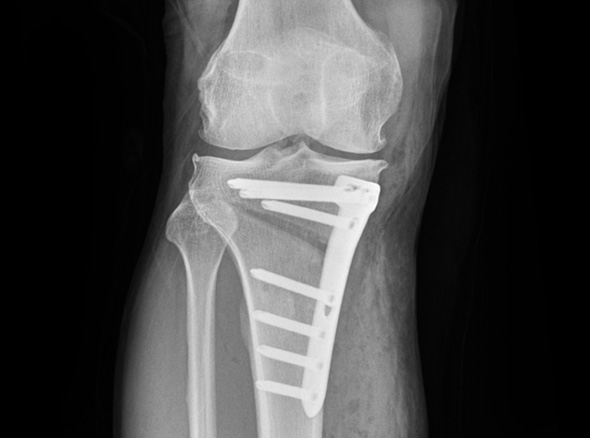

※ 금속판과 나사는 수술 후 약 1~2년 후 제거합니다.

관절내시경을 이용하여 연골재생이나 연골판에 필요한 치료를 시행한 후 경골(무릎 아래 뼈)의 근위부의

계획한 위치까지 절골을 시행한 후 뼈의 탄성을 이용하여 벌립니다. 그리고 금속판과 나사로 고정하여

수술 전 계획했던 X자형 또는 1자형 다리를 만들고 빈 공간에 뼈를 이식하여 골유합을 유도합니다.